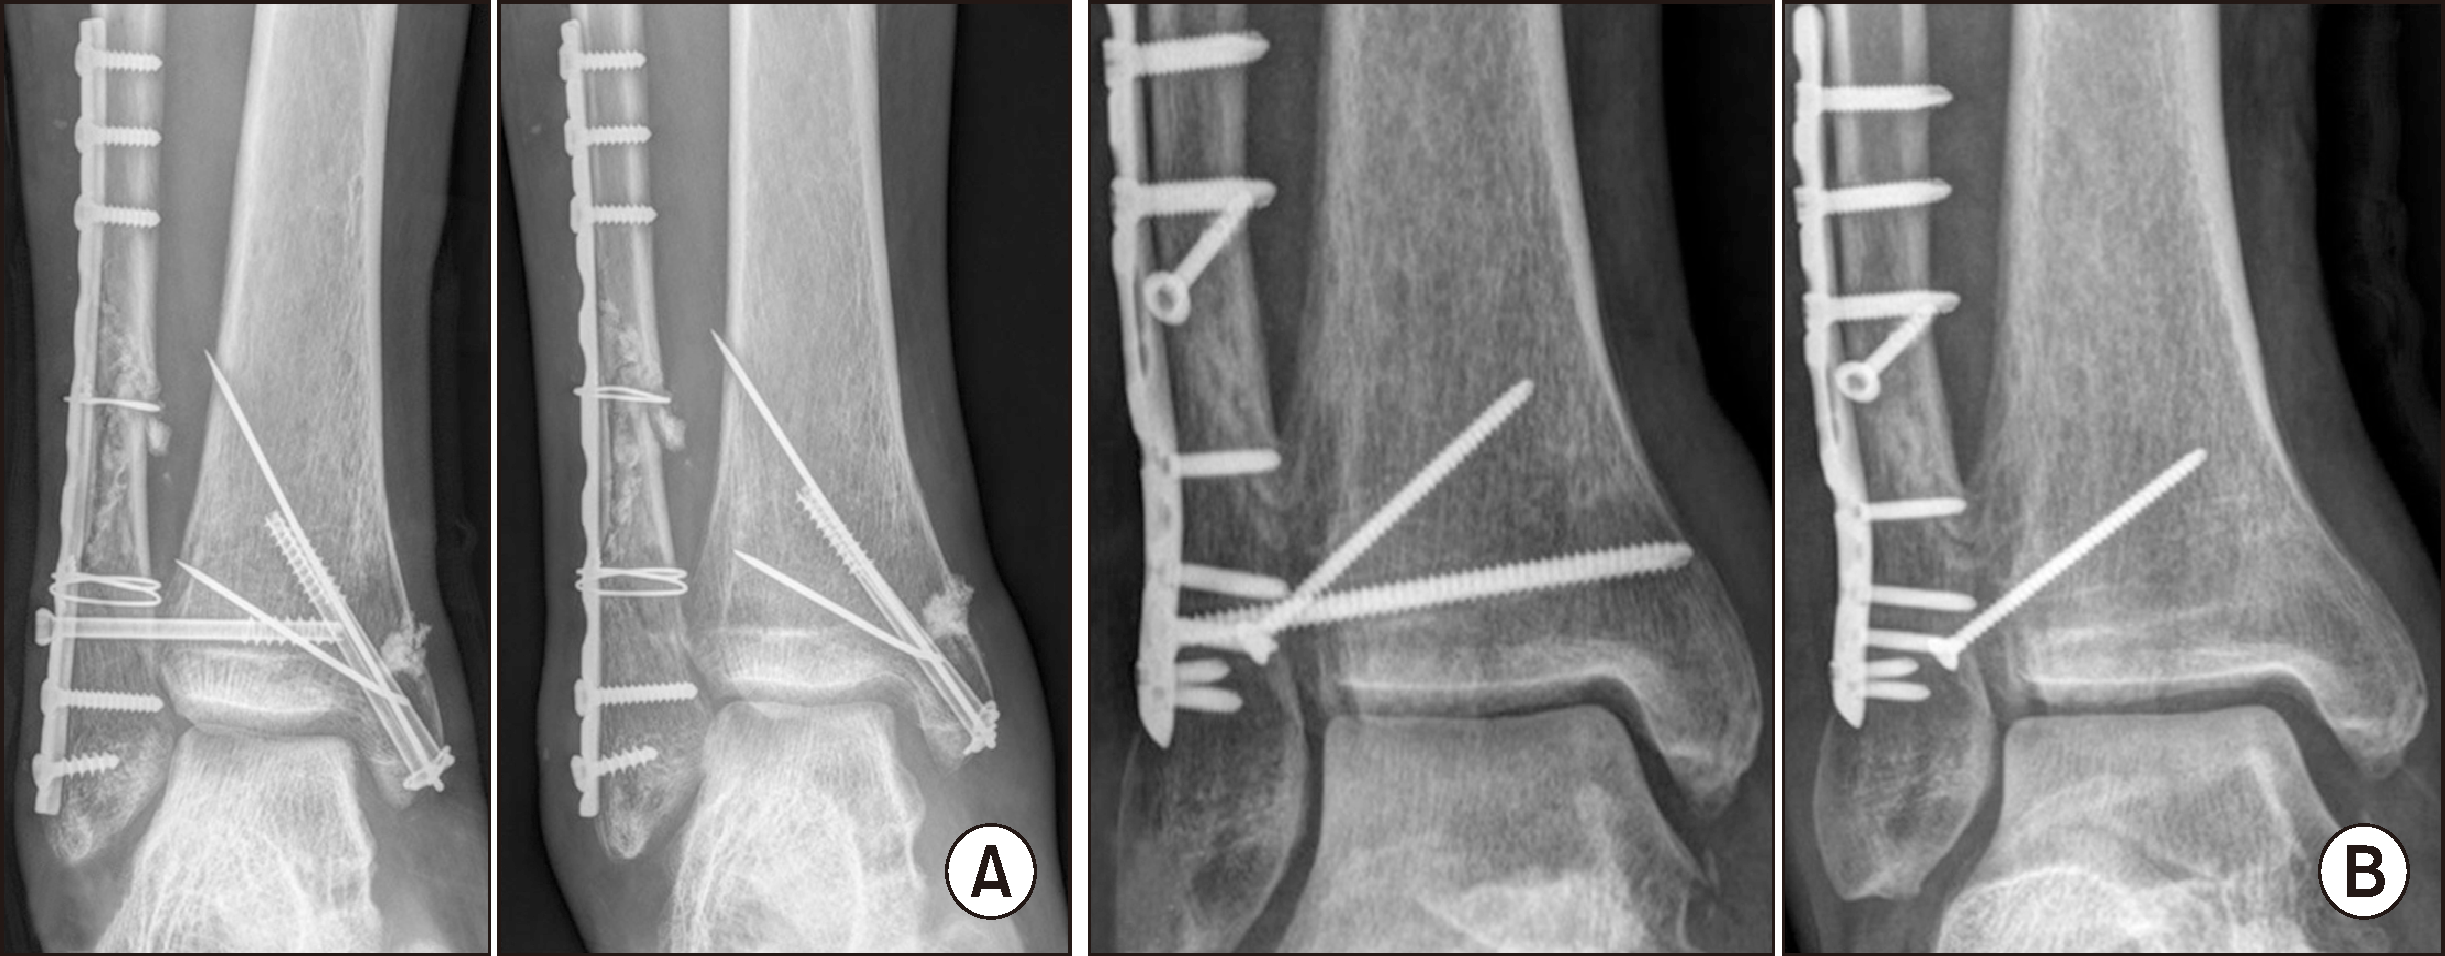

나사못 고정 수술의 경우 골절을 정복하고 내고정을 시행한 뒤 뼈 갈고리(bone hook)를 비골의 내측에 걸어 외측으로 당겨 영상 증폭기상에 경골과 비골 사이가 3∼4 mm 이상 벌어지는 경우에 수술을 시행하였다. 기존의 피부 절개를 통하여 족관절의 전방 원위경비골관절의 앞부분이 정복이 된 것을 확인 후에 손으로 정복을 유지하거나 겸자로 정복을 유지한 상태로 영상 증폭기로 원위경비 간격, 경비 겹침, 내측 빈 공간이 정상적으로 정복된 것을 확인 후 족관절을 중립 위치로 유지한 상태에서 수술하였다.10,11) 수술 시 전방 원위관절의 앞부분이 정복된 것을 확인하여 정복의 정확성을 기하였을 뿐 아니라 영상 증폭기 상의 mortise 영상에서 내측과 외측 그리고 상부 빈 공간이 동일한 것이 확인되었을 경우 관절면 2∼3 cm 상방에서 관절면에 평행하게 비골에서 경골 방향으로 20°∼30° 전방을 향하여 3개나 4개의 피질을 3.5 mm 피질골 나사못이나 4.0 mm 해면골 나사못 1개 내지 2개로 고정하였다(Fig. 1A). 정복은 다공증이 있어서 나사못이 단단히 삽입되지 않거나12) 골의 크기가 커서 견고히 고정되지 않는 경우에는 2개의 나사못을, 그렇지 않은 경우는 1개의 나사못을 삽입하였다.13) TightRope 봉합사 단추를 이용한 술식의 경우 동일한 방법으로 정복을 시행한 뒤 봉합사 단추가 통과할 수 있는 구멍을 뚫은 후 직사각형 단추를 구멍을 통해 반대측 내과로 빠져 나오게 하였고 끈을 당겨 직사각형 단추가 경골과 평행하게 된 것을 확인한 후 봉합사를 팽팽하게 당긴 뒤 고정하였다(Fig. 1B).

Figure 1

Examples of syndesmotic screw fixation (A) and suture button fixation (B) for syndesmosis injury.